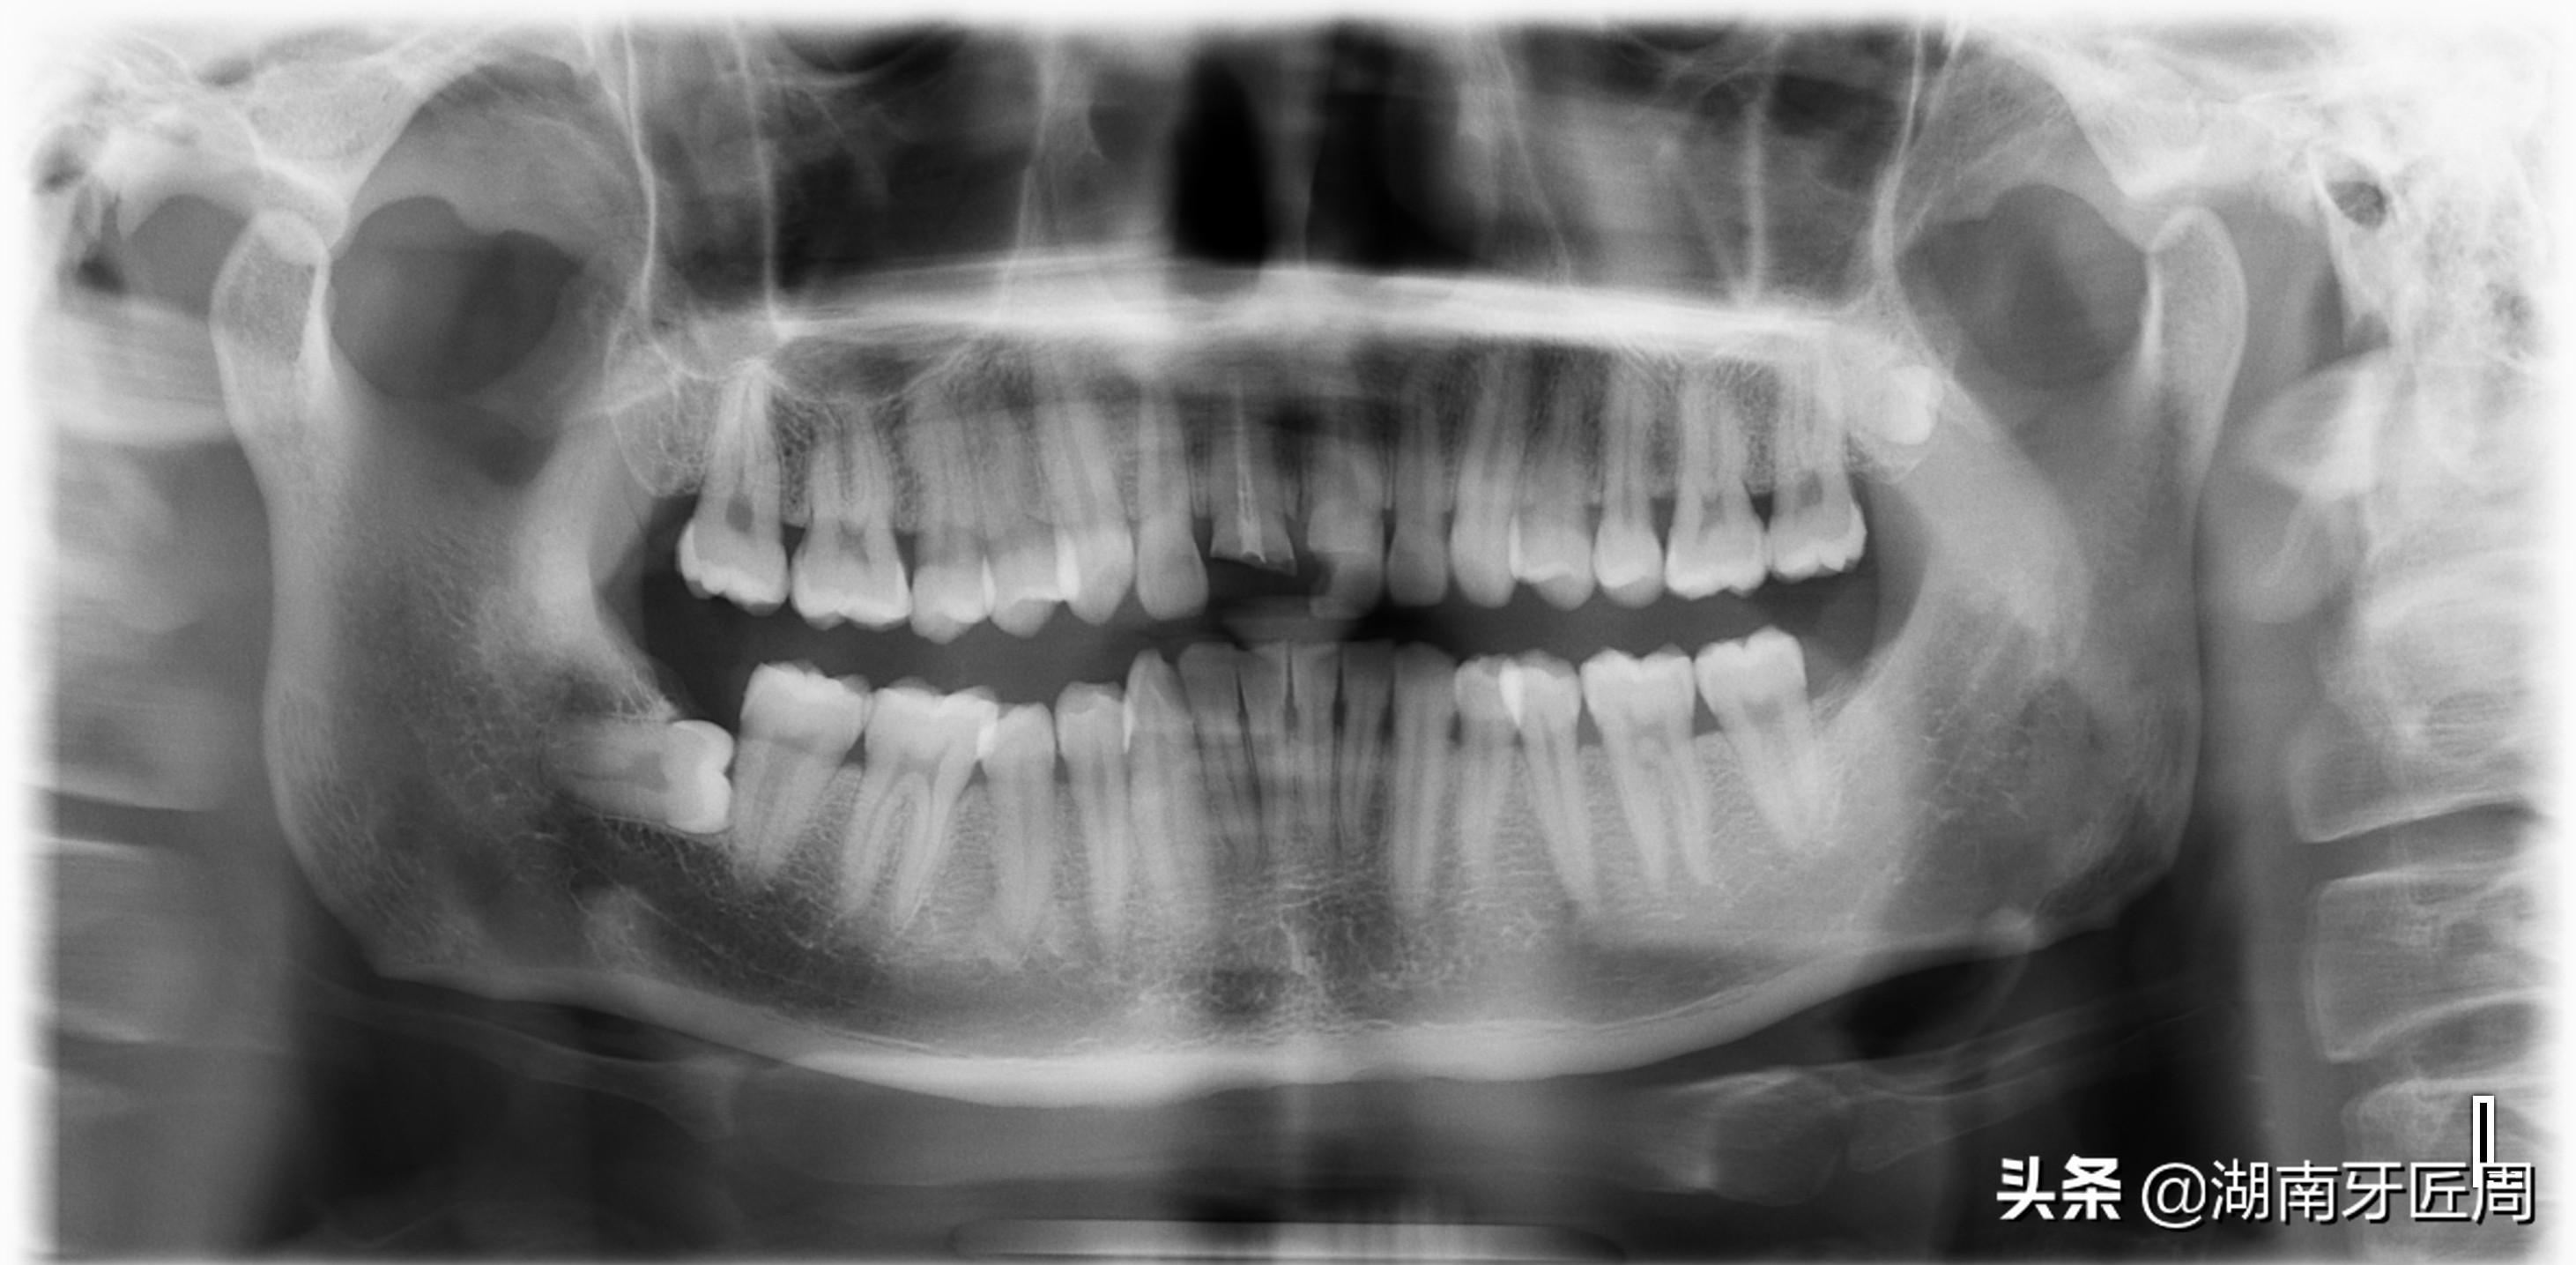

左侧智齿倾斜阻生,顶坏前牙

图片2.右侧智齿倾斜阻生顶坏前牙